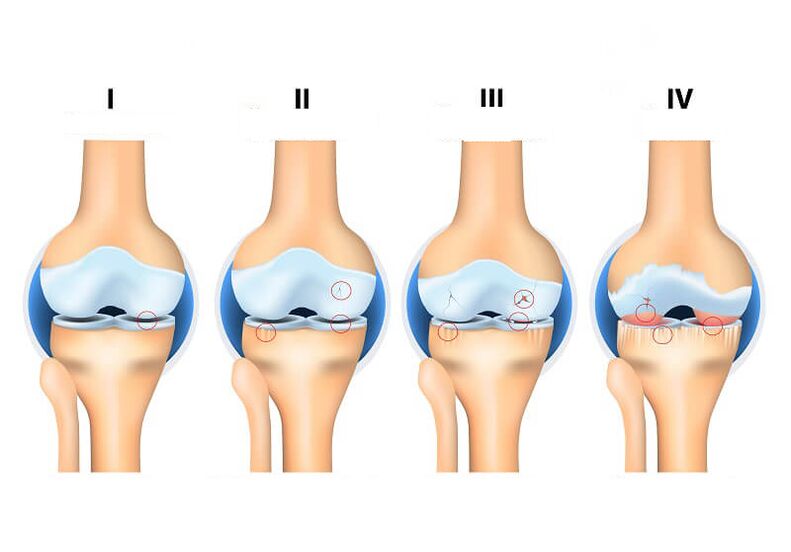

Artrozės stadijos

Artrozės ypatumas yra tas, kad ši liga sąnarį pažeidžia palaipsniui. Priklausomai nuo pakitimų, atsirandančių kremzliniame audinyje, išskiriami 4 sąnario artrozės laipsniai

1 laipsnio artrozė – Tai pradinė artrozės stadija. Šiame etape liga beveik nepasireiškia, o daugelis pacientų net neįtaria apie ligą.

2 laipsnių artrozė – pamažu ima ryškėti artrozė. Pacientas nerimauja dėl lengvo sąnarių skausmo, girdi traškėjimą ir jaučia nedidelį judesių standumą

3 laipsnių artrozė – stiprėja artrozės simptomai, progresuoja kremzlių irimas. Skausmas, judesių apribojimas, šlubavimas – nuolatiniai paciento, sergančio sąnarių artroze, palydovai. Jam sunku judėti savarankiškai, dirbti ar gyventi įprastą gyvenimo būdą.

4 laipsnių artrozė – pažengusi sąnarių artrozės stadija, kai visiškai sunaikinama sąnario kremzlė. Esant tokiai situacijai, neįmanoma išsiversti be sąnario pakeitimo.